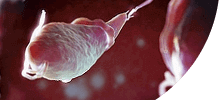

ПОПУЛЯЦИЯ +200,000

Самки паразитов откладывают до 240 000 яиц в кишечнике человека ежедневно.